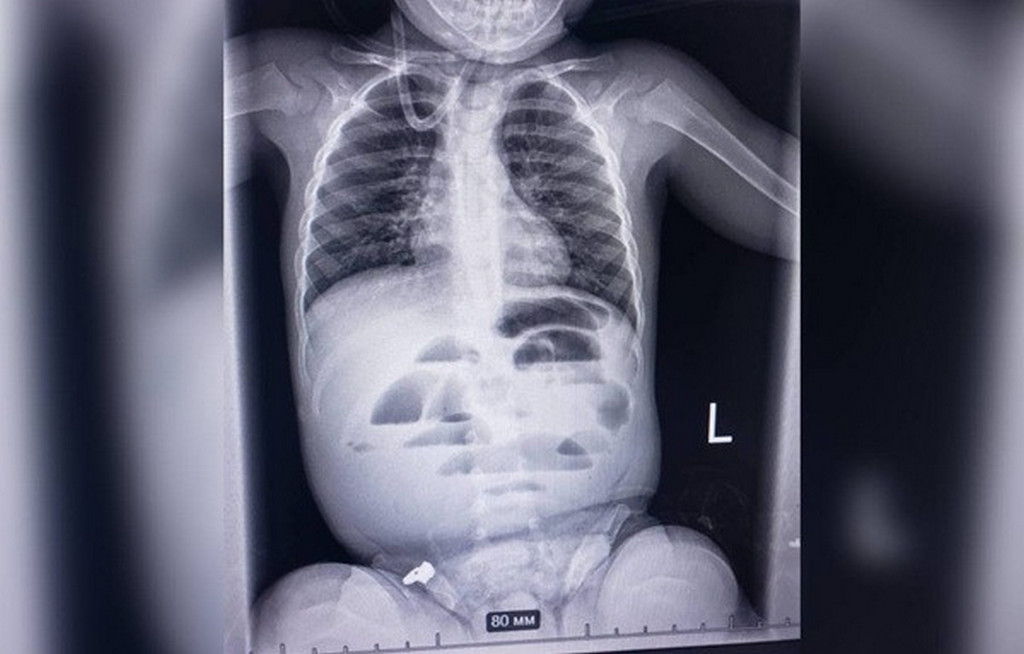

Малюка госпіталізували з підозрою на кишкову непрохідність. Під час обстеження рентген показав характерні ознаки цього стану, тож команда хірургів, анестезіологів і педіатрів ухвалила рішення негайно оперувати.

Під час втручання медики виявили стороннє тіло — гідрогелеву кульку діаметром близько 3 сантиметрів, яка повністю перекривала просвіт кишечника. Її видалили, після чого дитину перевели до реанімації для спостереження.